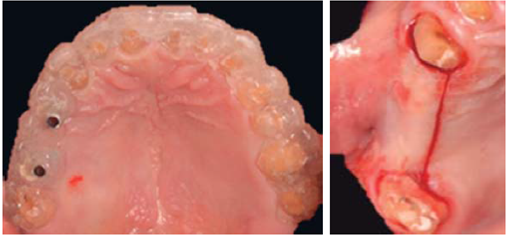

Este reporte documenta el tratamiento de un paciente masculino de 68 años de edad. Comenta tener dificultades masticatorias y digestivas debido a importante desgaste dental, se dice incómodo al sonreír; no refirió padecimientos sistémicos, fumó durante ocho años, diagnosticado con hipertensión arterial controlada. Se observa atrición generalizada, ausencia de dientes 14, 15, 16, 46 y periodonto sano (Figuras 1a4). Los dientes 13 y 37 presentaban tratamiento de conductos y periápice sano, sin restauración (Figura 5).

Con el objeto de restituir el diente 36 y en el caso de 37, dada la cercanía de su furca con la cresta ósea no fue posible ejecutar alargamiento de corona y así restaurarle, la osteoplastia de 3 mm necesaria para establecer el espacio correspondiente al espesor biológico hubiera desencadenado un defecto de furcación. Se procede a la planeación tomográfica para la colocación de dos implantes en la zona. Paralelamente se confecciona una guía quirúrgica restrictiva (Figura 13).

Se coloca implante marca BTI® en zona de 36 de 5 x 11.5 mm, torqueado a 40 N, e implante inmediato a la extracción, en zona de 37 de 5.5 x 13 mm con torque de 30 N (Figura 14).

Se efectuó regeneración ósea mediante colocación de membrana de colágeno y combinación de hueso autólogo colectado con protocolo de fresado biológico a 50 rpm acompañado de aloinjerto óseo de la marca Biograft® de 500 a 800 μm de partícula.5

Se colocaron tornillos tapa y consiguiendo cierre sin tensión del colgajo, se suturó con seda 4Ø. Se prosigue a la provisionalización de los implantes previo descubrimiento (Figura 15).

Mediante evaluación radiográfica de la relación corona-raíz, se realizó el alargamiento de la corona en el sextante anterosuperior para exponer suficiente estructura dental y lograr una retención adecuada para las restauraciones finales (Figuras 16a22).